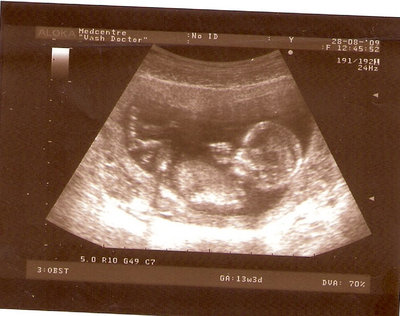

13 НЕД И 5 ДНЕЙ

3.jpg [ 96.81 КБ | Просмотров: 2456 ]

Nikisa писал(а): Foto prosto chudesnoe. A na kakom sroke uznali, chto sin.............. НА 13 НЕДЕЛЯХ.КАК РАЗ ВОТ В ЭТО узи, ОНО УМЕНЯ ВТОРОЕ БЫЛО. ЭТО КОНЕЧНО МАЛЕНЬКИЙ СРОК ДЛЯ ОПРЕДЕЛЕНИЯ ПОЛА. НО Я ПОПРОСИЛА ВРАЧА(ЭТО КТСТАТИВ РОССИИ БЫЛО) ХОТЯ БЫ ПРЕДПОЛОЖИТЬ. ЕЙ ВСЁ ТАКИ УДАЛОСЬ РАССМОТРЕТЬ.НУ ВООБЩЕМ ЧЕРЕЗ НЕСКОЛЬ ДНЕЙ ПОЙДУ К ВРАЧУ, УЖЕ АМЕРЕКАНСКОМУ И УЗНАЮ ТОЧНО. К ТОМУ ВРЕМЕНИ У МЕНЯ БУДЕТ СРОК 18 НЕДЕЛЬ. ХОТЕЛОСЬ БЫ ПОСМОТРЕТЬ НА ДРУГИЕ ФОТО НА ЭТОМ СРОКЕ ИЛИ БОЛЬШЕ. ТАК ЧТО ВЫКЛАДЫВАЙТЕ, ЕСЛИ НЕ ЖАЛКО!